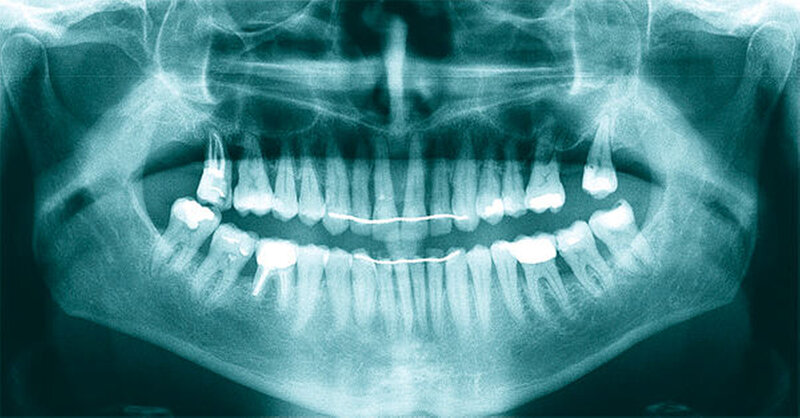

Die Sulkustiefen konnten auf etwas weniger als 4 mm reduziert werden, während der Blutungs- und Plaque-Index bei weniger als 15 Prozent lag. Daher wurde eine kieferorthopädische Behandlung über die nächsten zwei Jahre in Kombination mit engen zahnärztlichen Kontrollen geplant. Als Mittel der Wahl entschieden wir uns gemeinsam mit dem Patienten für das Invisalign-System, da hiermit sowohl eine Schienung als auch eine kraft-arme Bewegung der Zähne möglich sein sollte. Für den Frontzahnbereich wurden keine Attachments geplant, so dass hier eine unnötige Hebelwirkung umgangen werden konnte (Abbildung 3).

Um einen kompletten Lückenschluss im Oberkiefer zu ermöglichen, musste im Unterkieferfrontzahnbereich zusätzlich zur Derotation und Positionierung der Zähne – insbesondere Zahn 41 – von approximaler Schmelzreduktion, kurz ASR , Gebrauch gemacht werden, um einer Tonn`schen Diskrepanz entgegenzuwirken (siehe dazu Abbildung 7 auf Seite xy).

Nach Ausgliederung der insgesamt 14 Invisalignschienen, die der Patient jeweils drei Wochen getragen hatte, wurden ihm sowohl im Unter- als auch im Oberkiefer Sechs-Punkt-Retainer eingegliedert, um eine Schienung und Stabilisierung der Zähne untereinander zu ermöglichen.